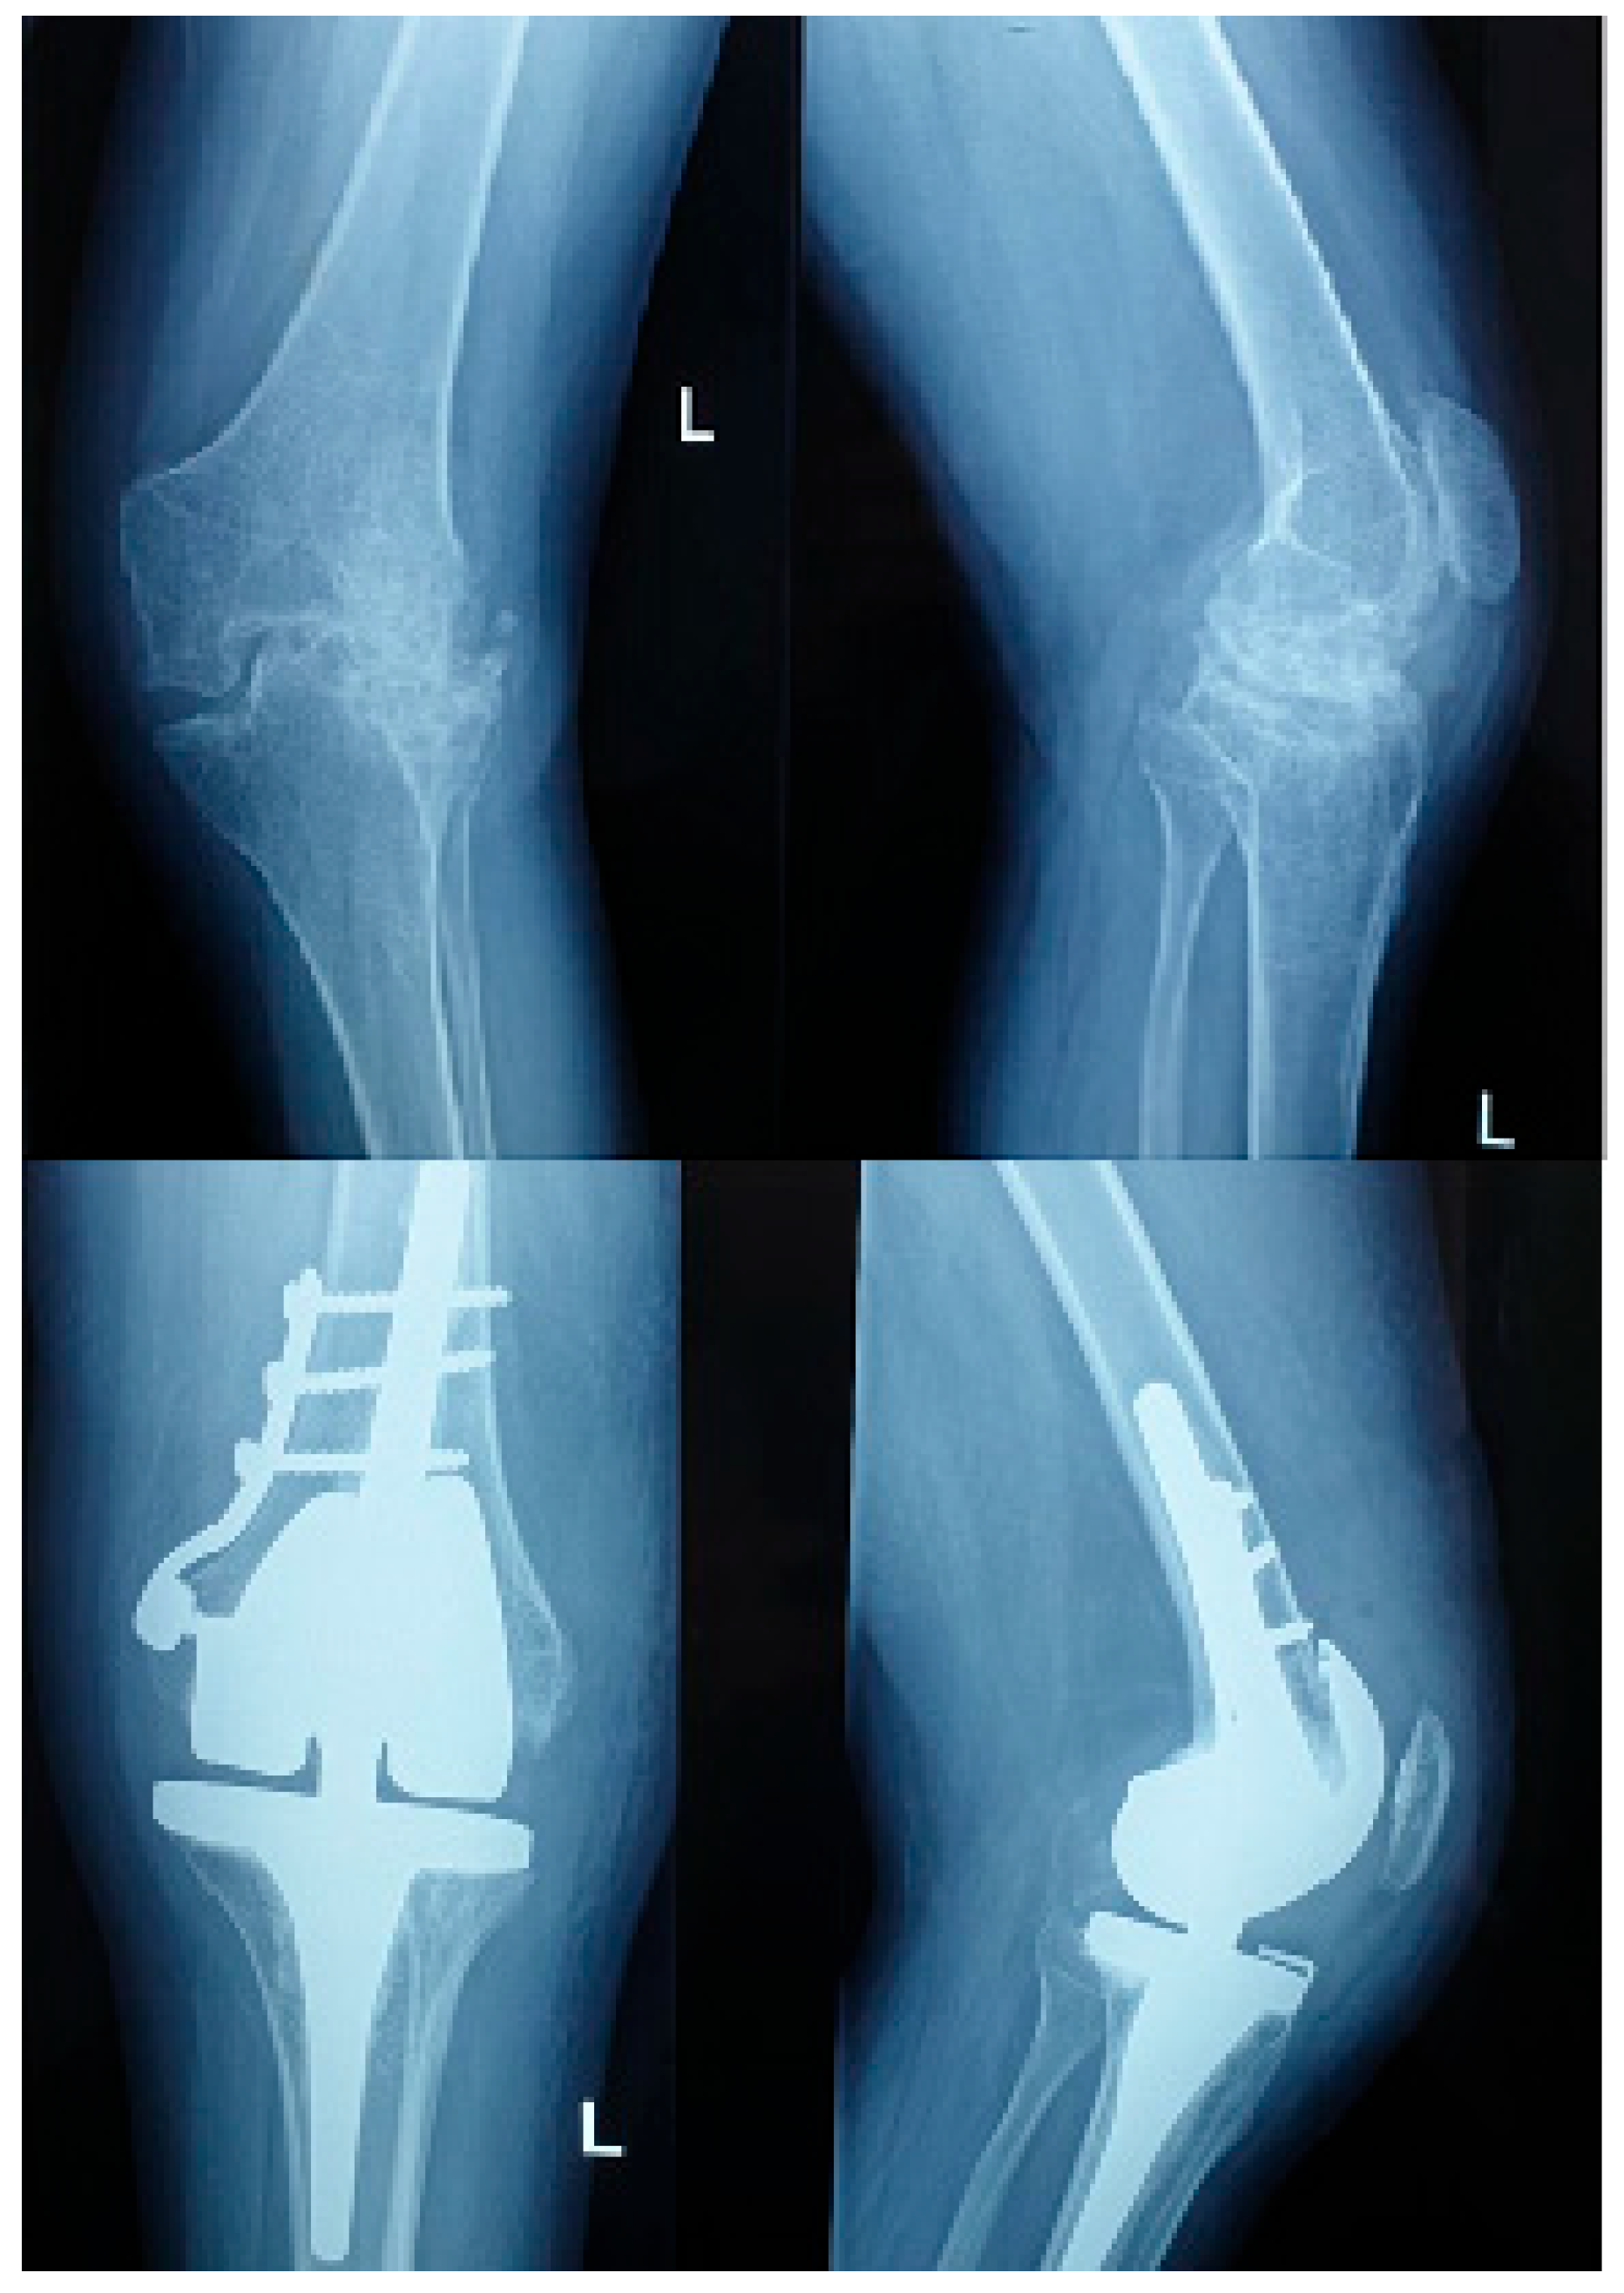

Complications occurred in 90% of hemophilic and 20% of non-hemophilic patients. According to the Clavien–Dindo classification, most events were Grades I–II, including anemia managed conservatively or with transfusion. Grade III complications included five compressive hematomas requiring surgical evacuation, three cases of wound dehiscence necessitating revision, and one intraoperative femoral condyle fracture (Grade IIIb) stabilized with plate and screws. No Grade IV (life-threatening) or Grade V (death) events were observed. (Figure 1).

Among the 20 hemophilic patients, three (15%) had factor inhibitors—two pre-existing and one developing postoperatively. Compared with inhibitor-negative patients, those with inhibitors exhibited markedly more complex perioperative courses. The mean operative time was prolonged (172.0 ± 6.5 min vs. 151.2 ± 17.9 min, p = 0.048), and the transfusion requirement was higher (100% vs. 37.5%, p = 0.021). The mean hospital stay was significantly longer (15.7 ± 2.1 days vs. 11.8 ± 2.2 days, p = 0.012). All inhibitor-positive patients developed postoperative complications: two experienced compressive hematomas requiring surgical evacuation (Clavien–Dindo Grade IIIb), and one sustained an intraoperative medial femoral condyle fracture, stabilized with plate and screws (Grade IIIb).

Figure 1. Pre and postoperative X ray of a hemophilic patient with inhibitors.